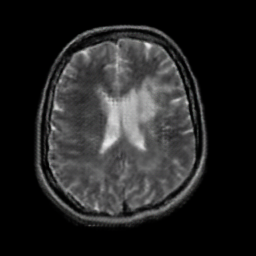

In this paper, we propose a bidirectional learning model, known as dual contrast cycleGAN (DC-cycleGAN), for medical image synthesis from unpaired data. Specifically, a dual contrast (DC) loss is formulated that leverages the advantage of samples from the source domain as negative samples to indirectly build constraints between real source and synthetic images via discriminators, and synthesize images more related to the target domain by enforcing the synthetic images to fall far away from the source domain. In addition, structural similarity index (SSIM) [35] and cross-entropy (CE) [48] are integrated into the DC-cycleGAN structure to avoid disappearing gradient information that is caused by a mean absolute error (MAE) and synthesizing irrelevant images. SSIM considers luminance [35] and CE converges fast as its back-propagation error is less than MSE [28]. As can be seen in Figs. 1 and 2, using SSIM and CE with dual contrast can generate more clear and accurate MR images as compared with that of MAE and MSE, and SSIM and CE without dual contrast loss. Although both SSIM and CE with dual contrast and without dual contrast generate similar CT images, SSIM and CE with dual contrast quantitatively generate better images as shown in Table 4. The experimental results indicate that DC-cycleGAN is able to consider more complex features such as structure in synthesizing images and produce remarkable results as compared with other state-of-the-art methods reported in the literature.

Tables 3 and 4 show the results of MR and CT synthesis, respectively. As can be seen, all components play vital role in both tables. SSIM & CE (w) performs significantly better than other losses in synthesizing MR images. This also can be seen visually in Fig. 1. In contrast, SSIM&CE (w) performs slightly better than SSIM&CE (wo) in synthesizing CT images, both generate more or less similar CT images (see Table 4).